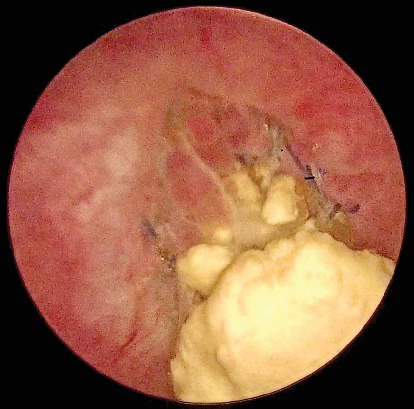

Tension-free vaginal tape has been the gold standard for the treatment of stress urinary incontinence for over 20 years. However, rare complications like intravesical tape erosion can significantly reduce quality of life, requiring surgical removal. This procedure must preserve continence and can be challenging. We report the case of a 53-year-old woman who presented with recurrent urinary tract infections and dysuria 7 years after a TVT procedure. Imaging revealed a bladder stone attached to the eroded sling at the bladder neck, inaccessible via standard cystoscopy. A transvesical laparoscopic approach was used to successfully remove the intravesical portion of the tape. The patient recovered well and remained symptom-free and continent. Various techniques are used to perform intravesical tape resection. Transvesical laparoscopy offers excellent visualization and precise excision and minimizes recurrence risks for stress urinary incontinence. It is a safe, effective, and minimally invasive option for removing eroded tension-free vaginal tape, especially in difficult-to-access areas like the bladder neck.

Abstract Image